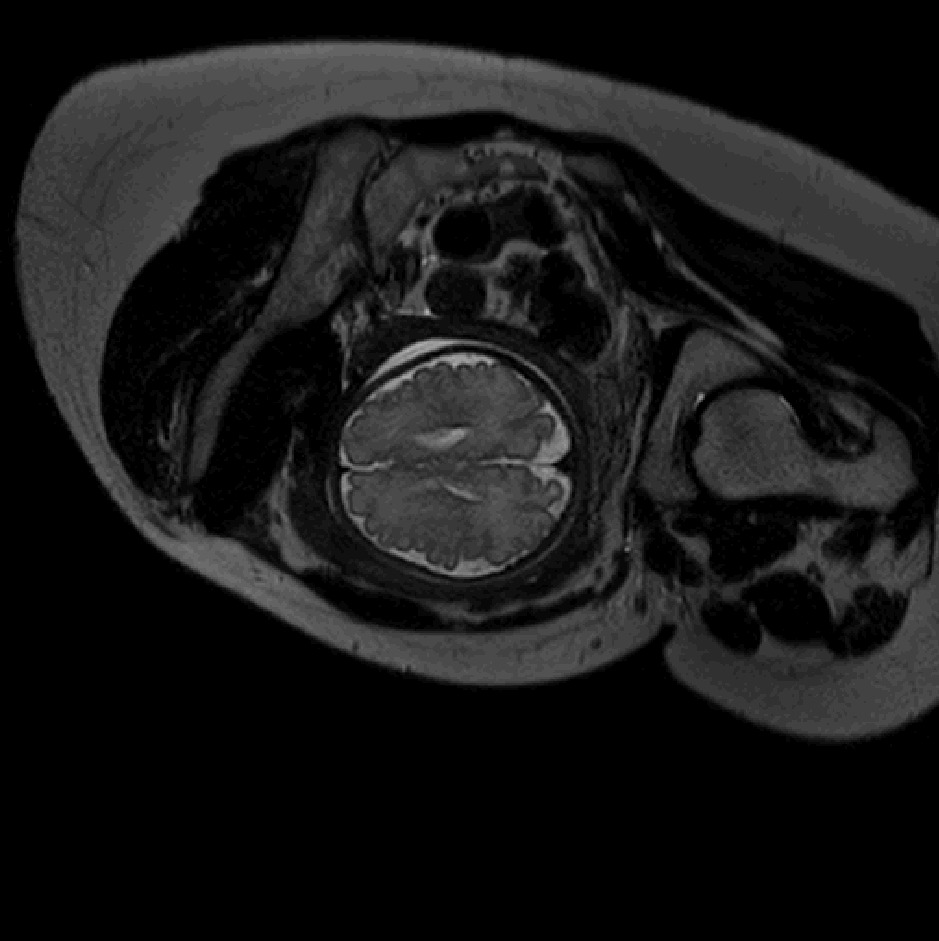

Table 1 lists average of quantitative evaluation results of these experiments and Figure 2 shows results obtained from each image. Figure 3 shows examples of the obtained segmentations.

Refer to caption

Figure 3: Example of ICV segmentations in images acquired in axial (left), coronal (middle) and sagittal (right) planes. Top row: A slice from T2-weigted image; Second row: Automatic segmentations obtained using 7 training images from the representative imaging planes; Third row: Automatic segmentations obtained using all 21 training images from all 3 image orientations; Bottom row: Manual segmentation.